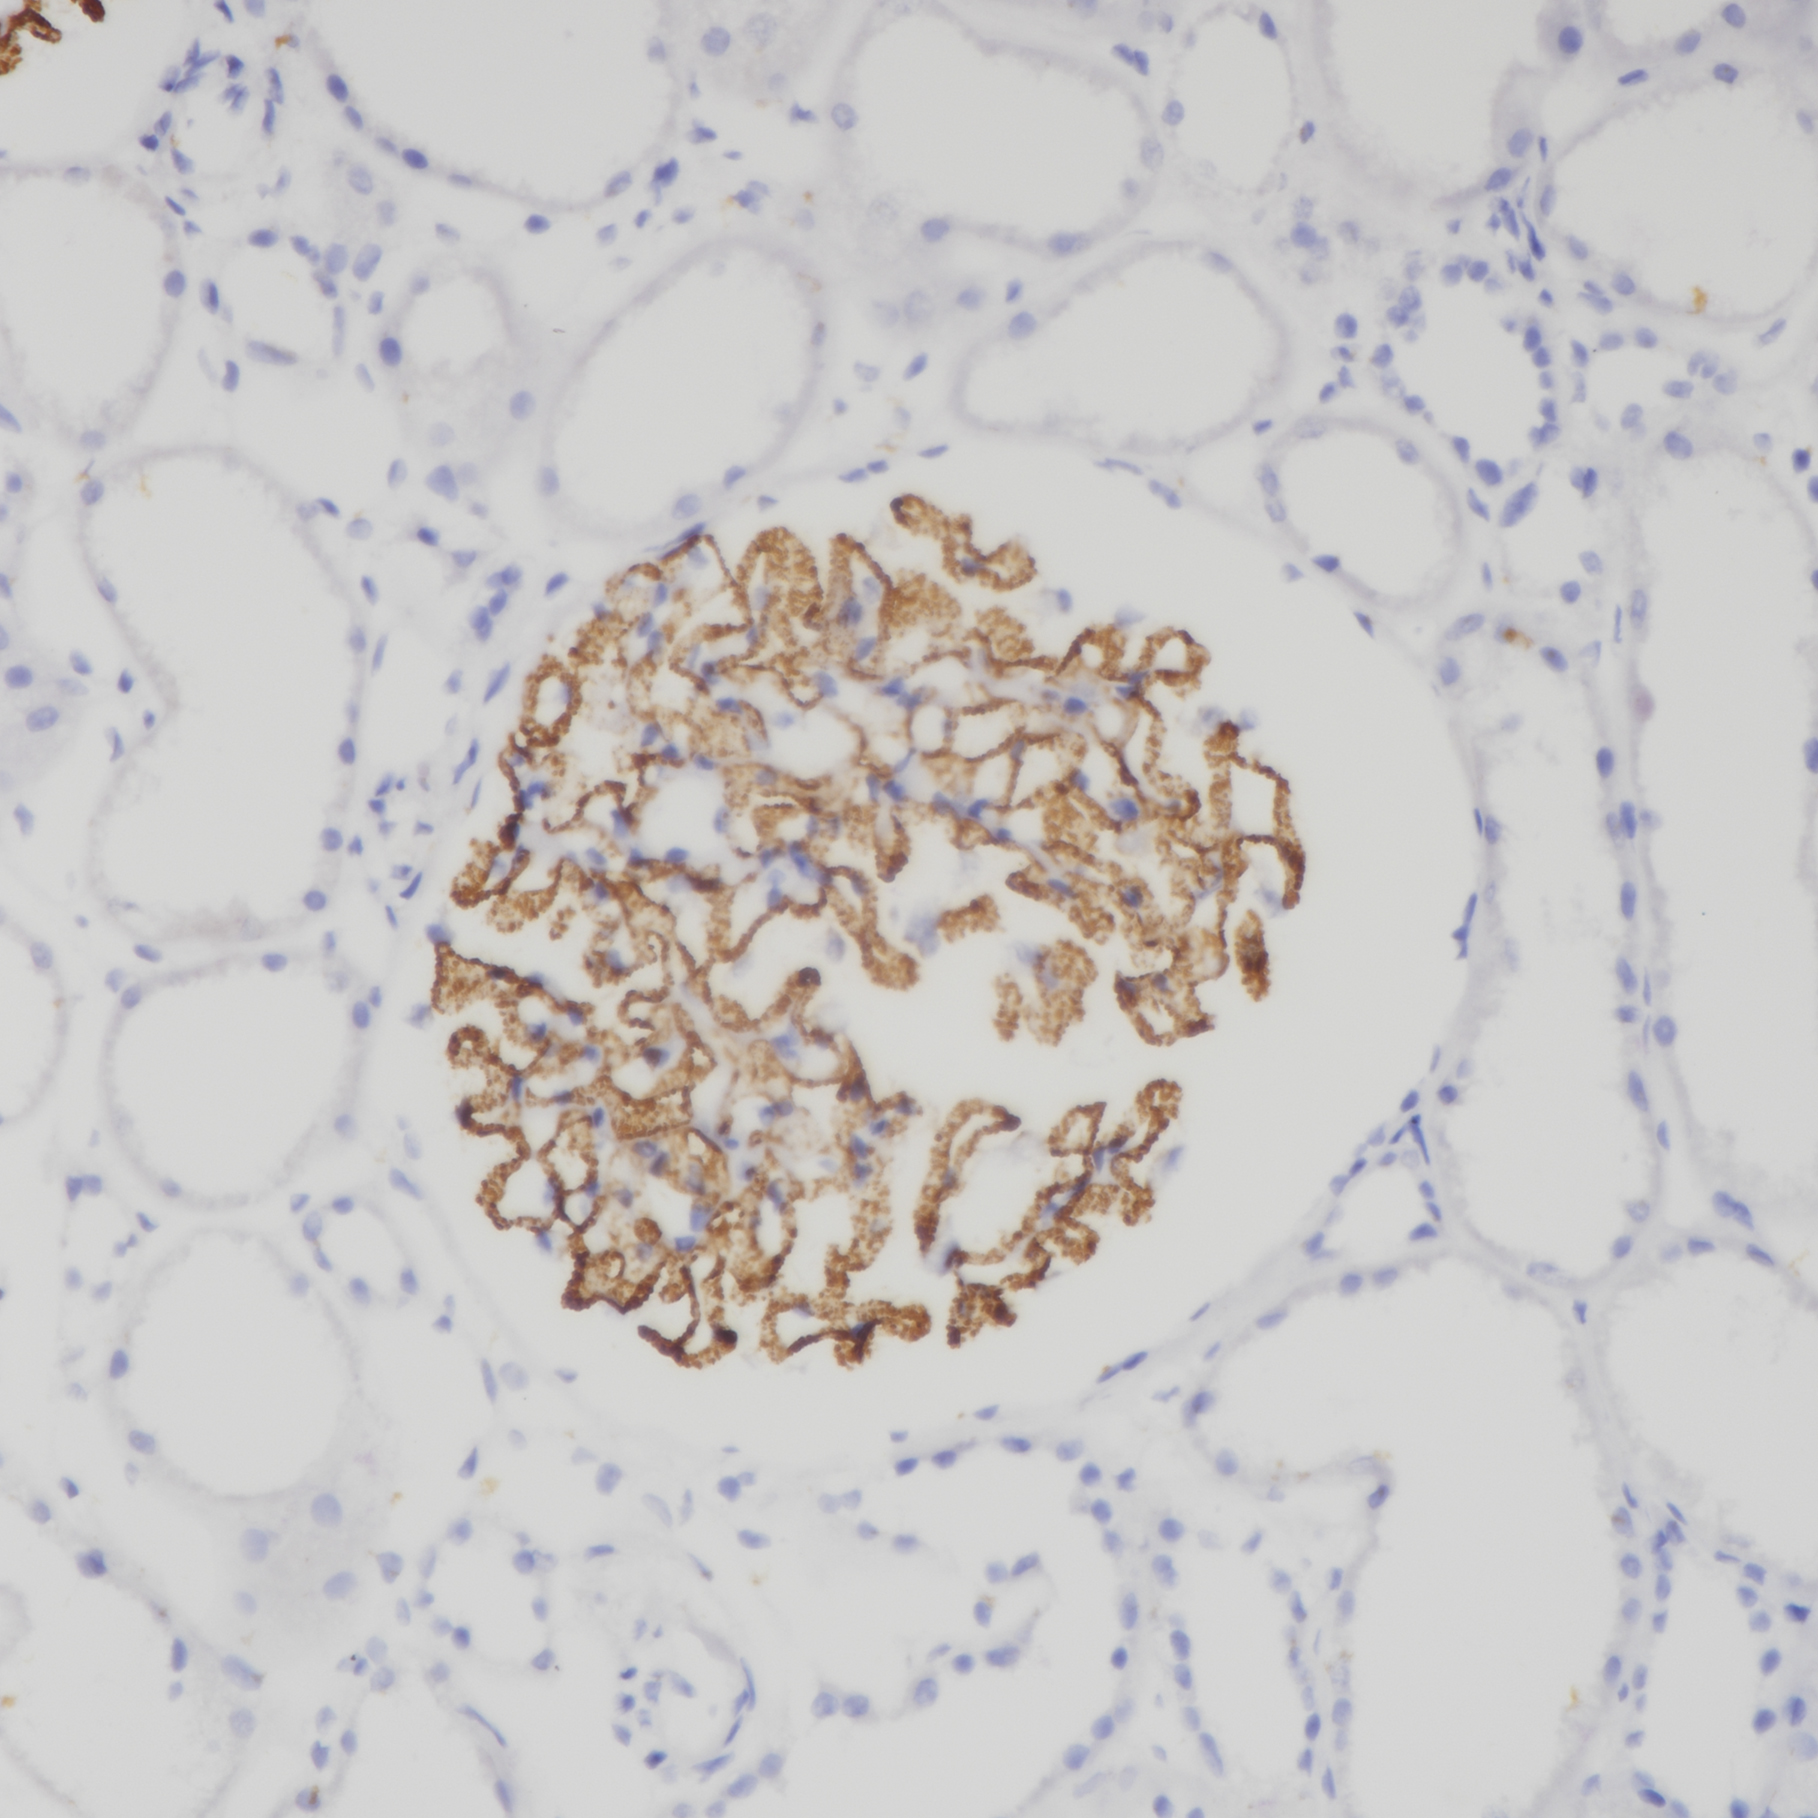

1. Mesquita R A , Araújo, Vera Cavalcanti de, Paes, Roberto Antônio Pinto, et al. Immunohistochemical analysis for CD21, CD35, Caldesmon and S100 protein on dendritic cells types in oral lymphomas[J]. J. Appl. Oral Sci. 2009, 17.